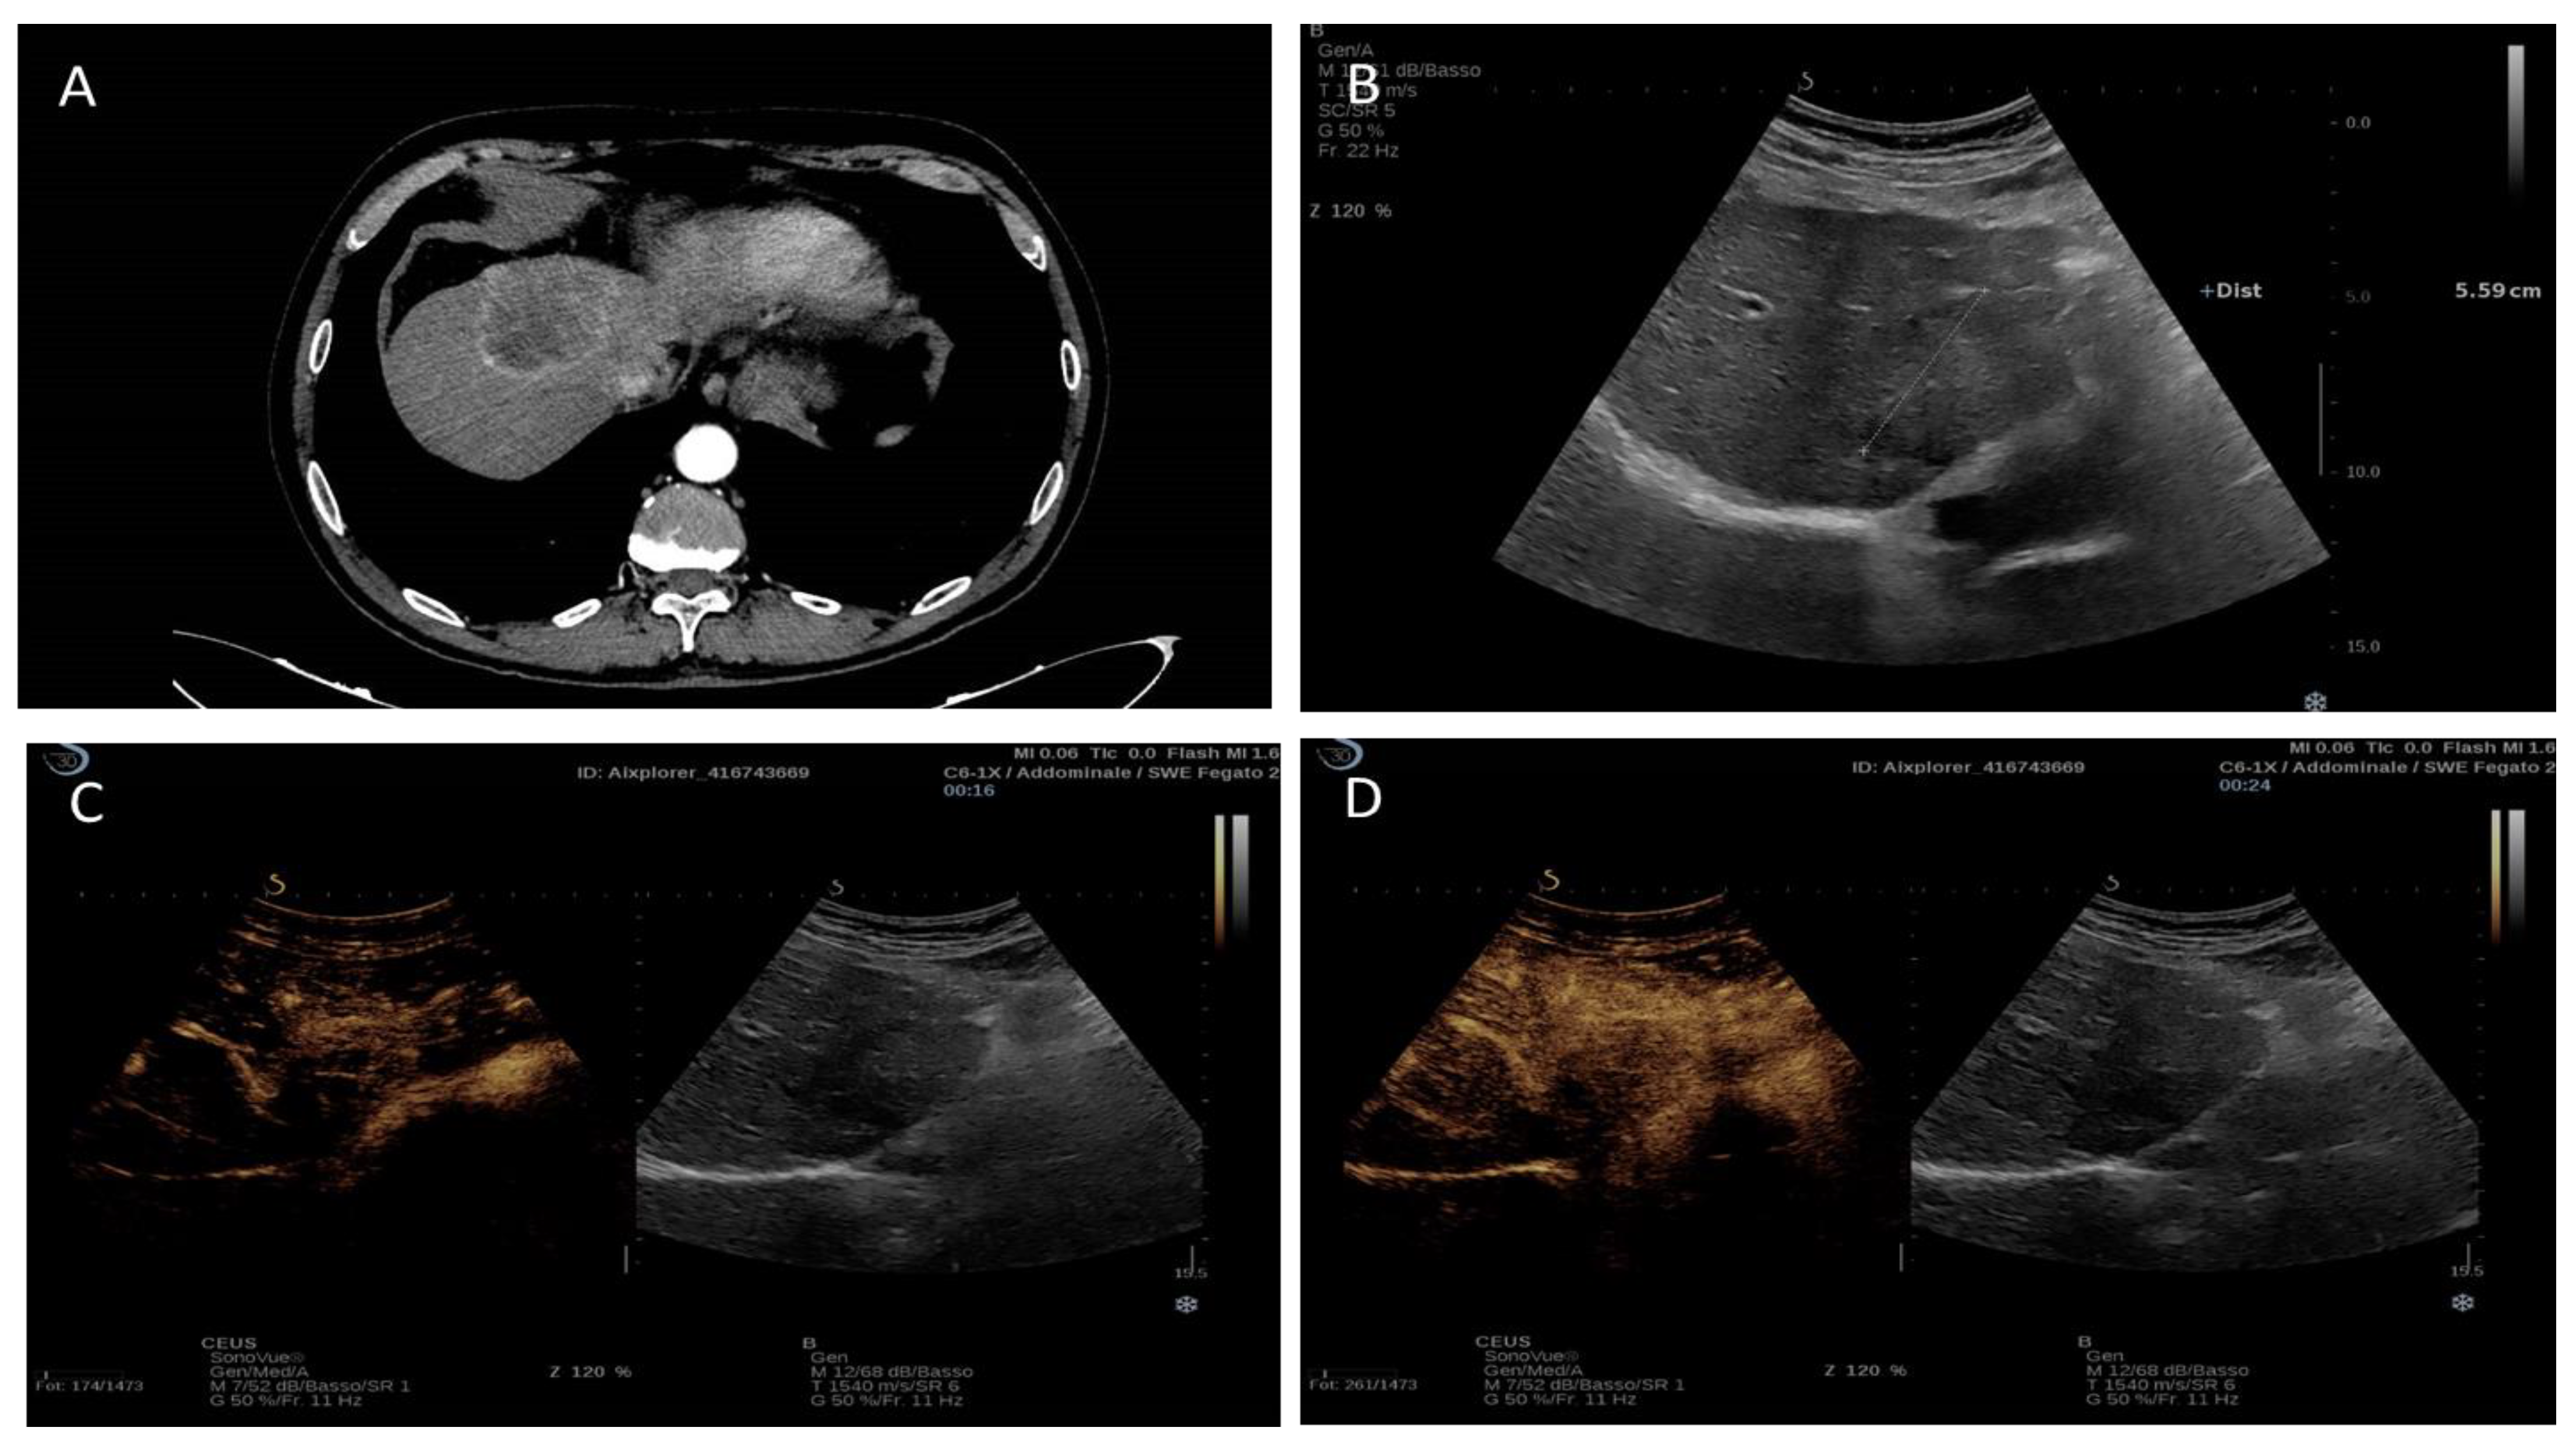

1.4. Contrast-Enhanced Ultrasound (CEUS)